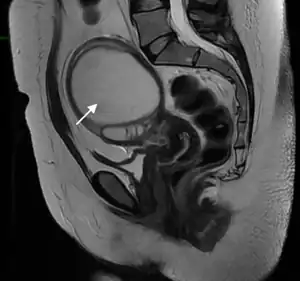

Pelvic abscess in a 32 years old women